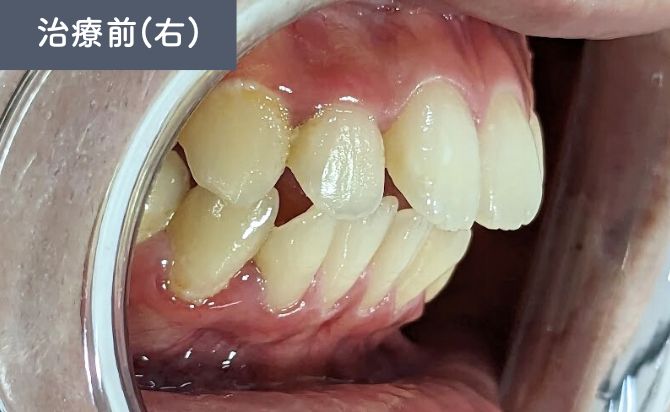

歯並びの変化(右)

治療終了時には、上顎前歯の前突が改善し、

唇元の突出感が軽減したことで横顔のバランスも向上しました。

歯列全体のアーチも整い、前歯の噛み合わせが適切な位置に改善。見た目だけでなく、機能的にも安定した咬合が得られています。